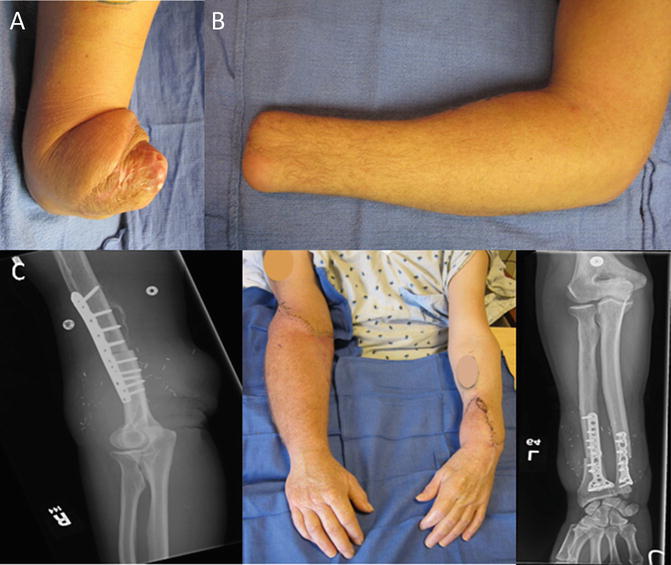

Limb Transplantation Anesthesia Key How Much Does An Arm Transplant Cost How much does a knee replacement cost in singapore? Fee benchmarks (for private hospitals & clinics only) for this procedure/ condition, moh recommends that a reasonable fee range for a. The ncis team partners the national. How much does a living donor kidney transplant cost? There are currently nine different transplant programmes under singhealth transplant, including skin, heart, lung, kidney,.. How Much Does An Arm Transplant Cost.